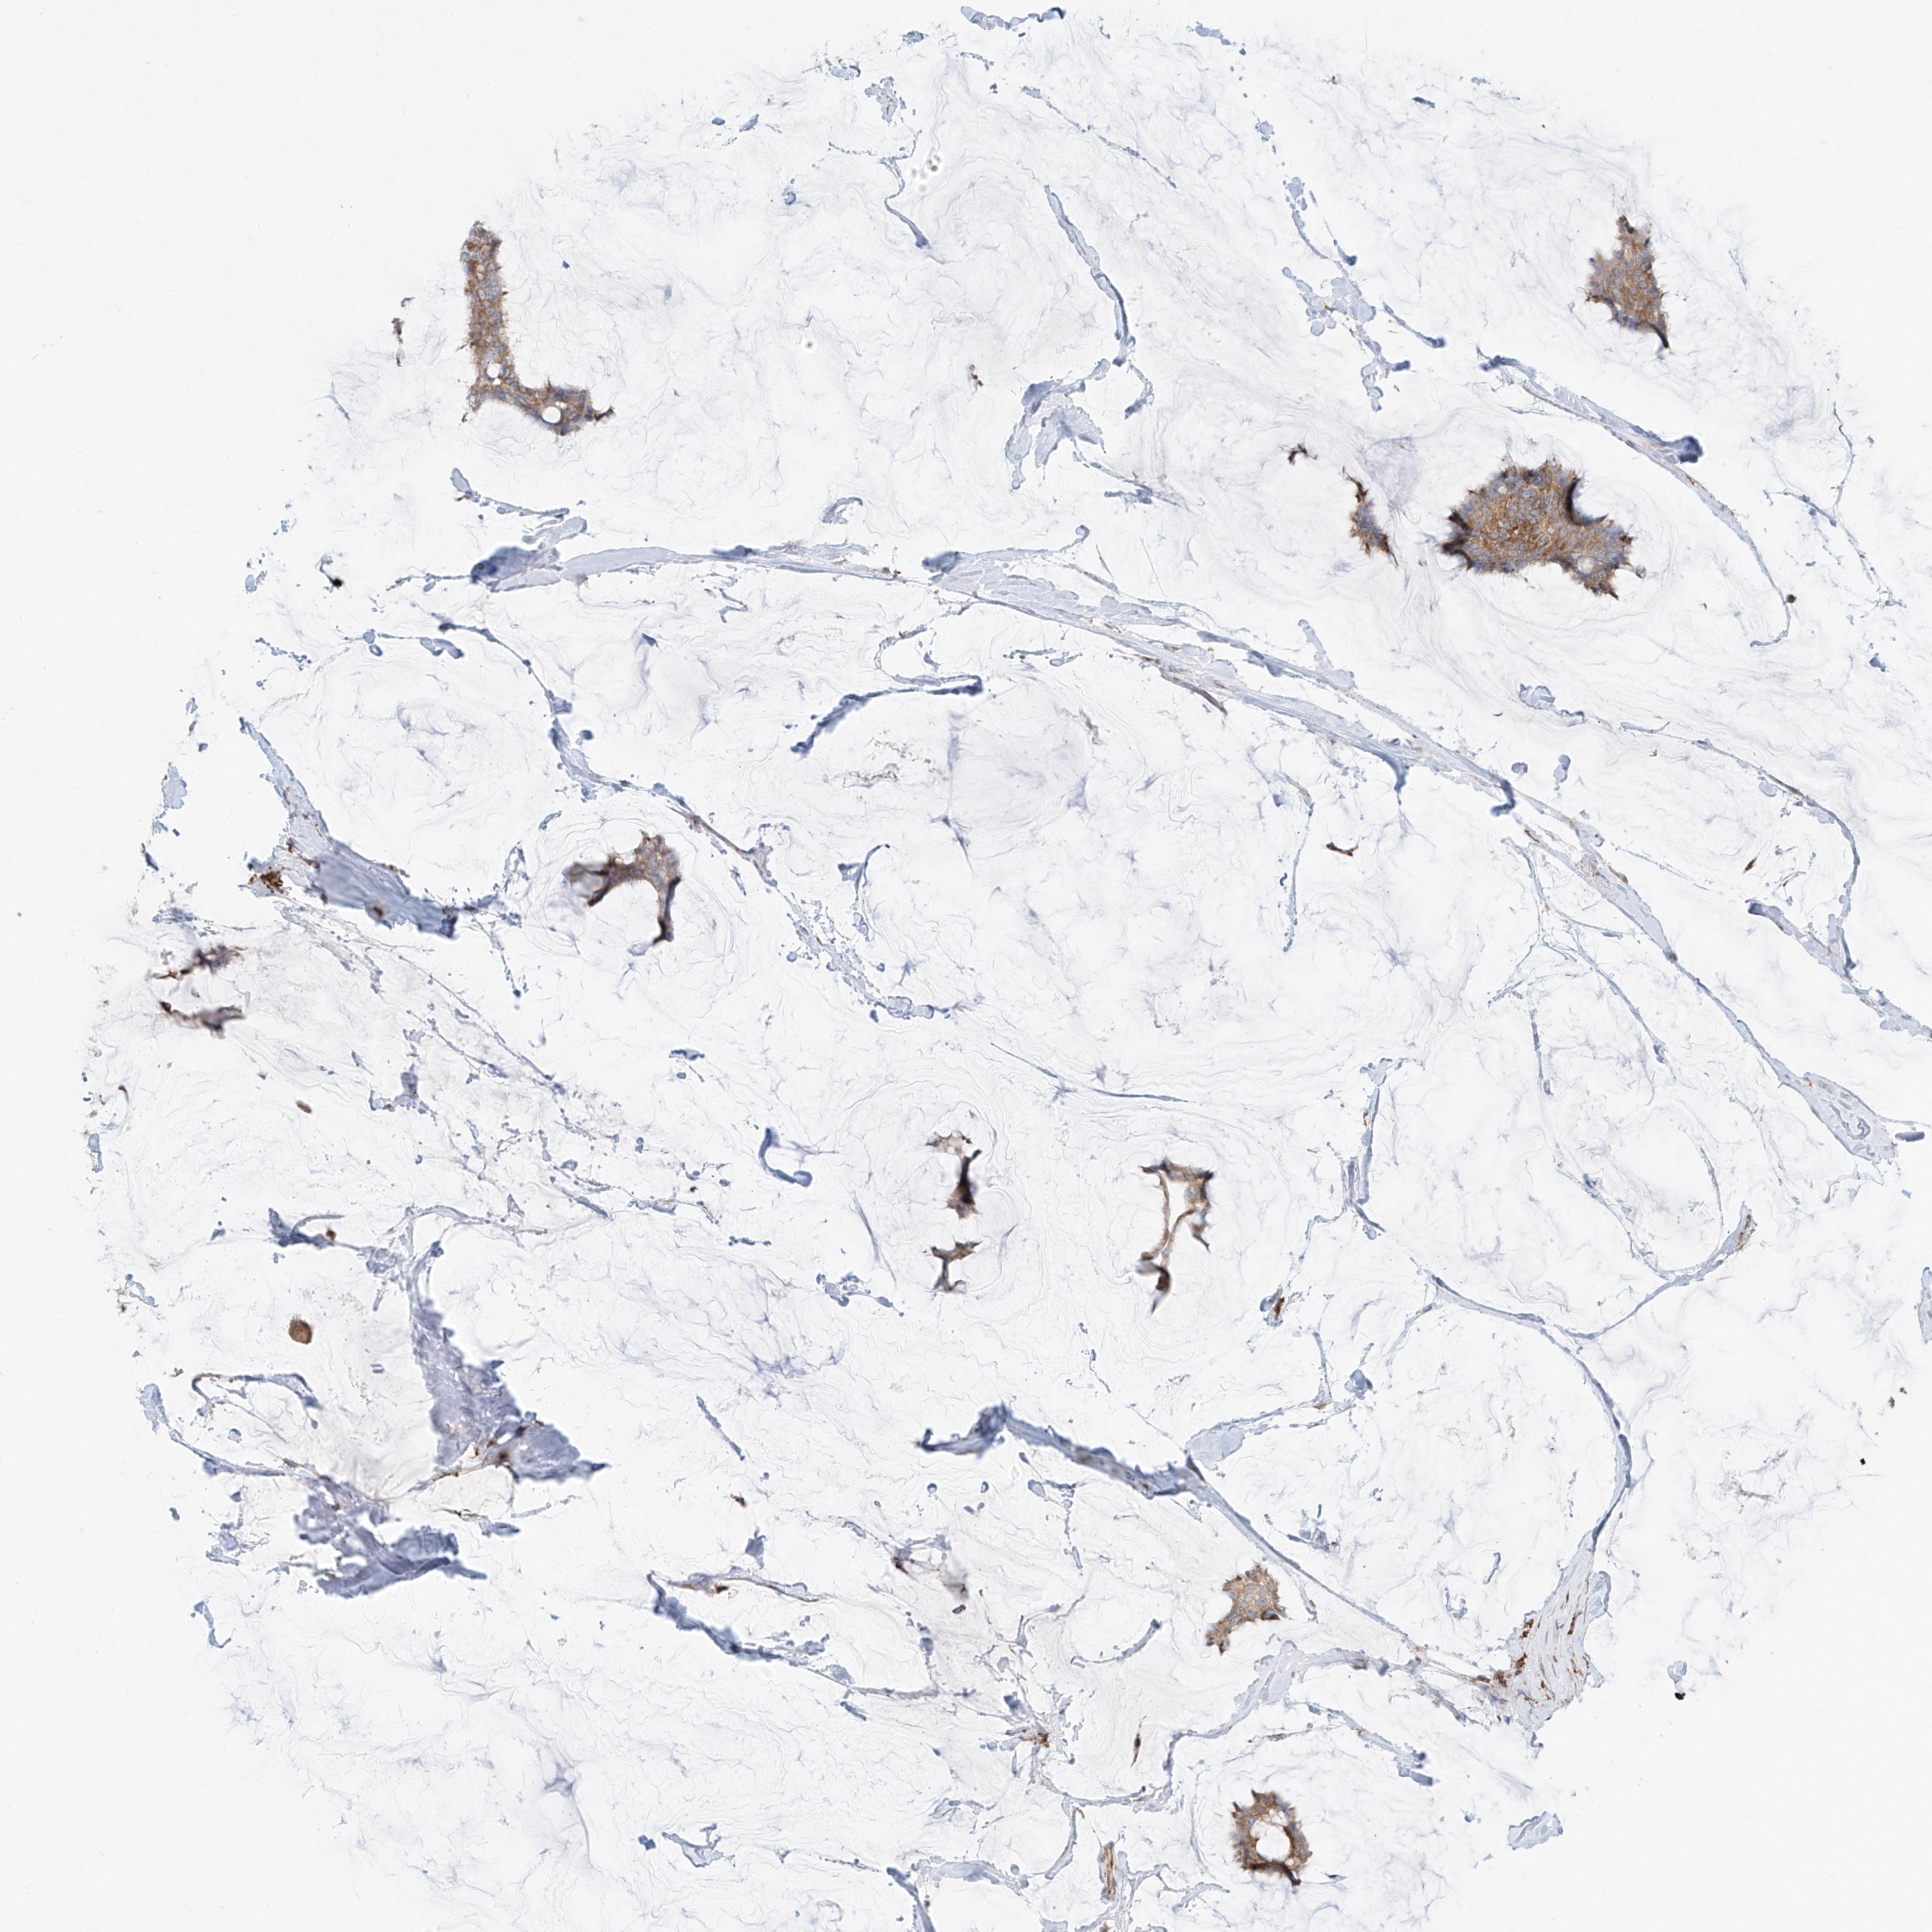

CANCER BREAST CANCER Show tissue menu

BRCA TCGA BRCA VALIDATION PROTEIN EXPRESSION